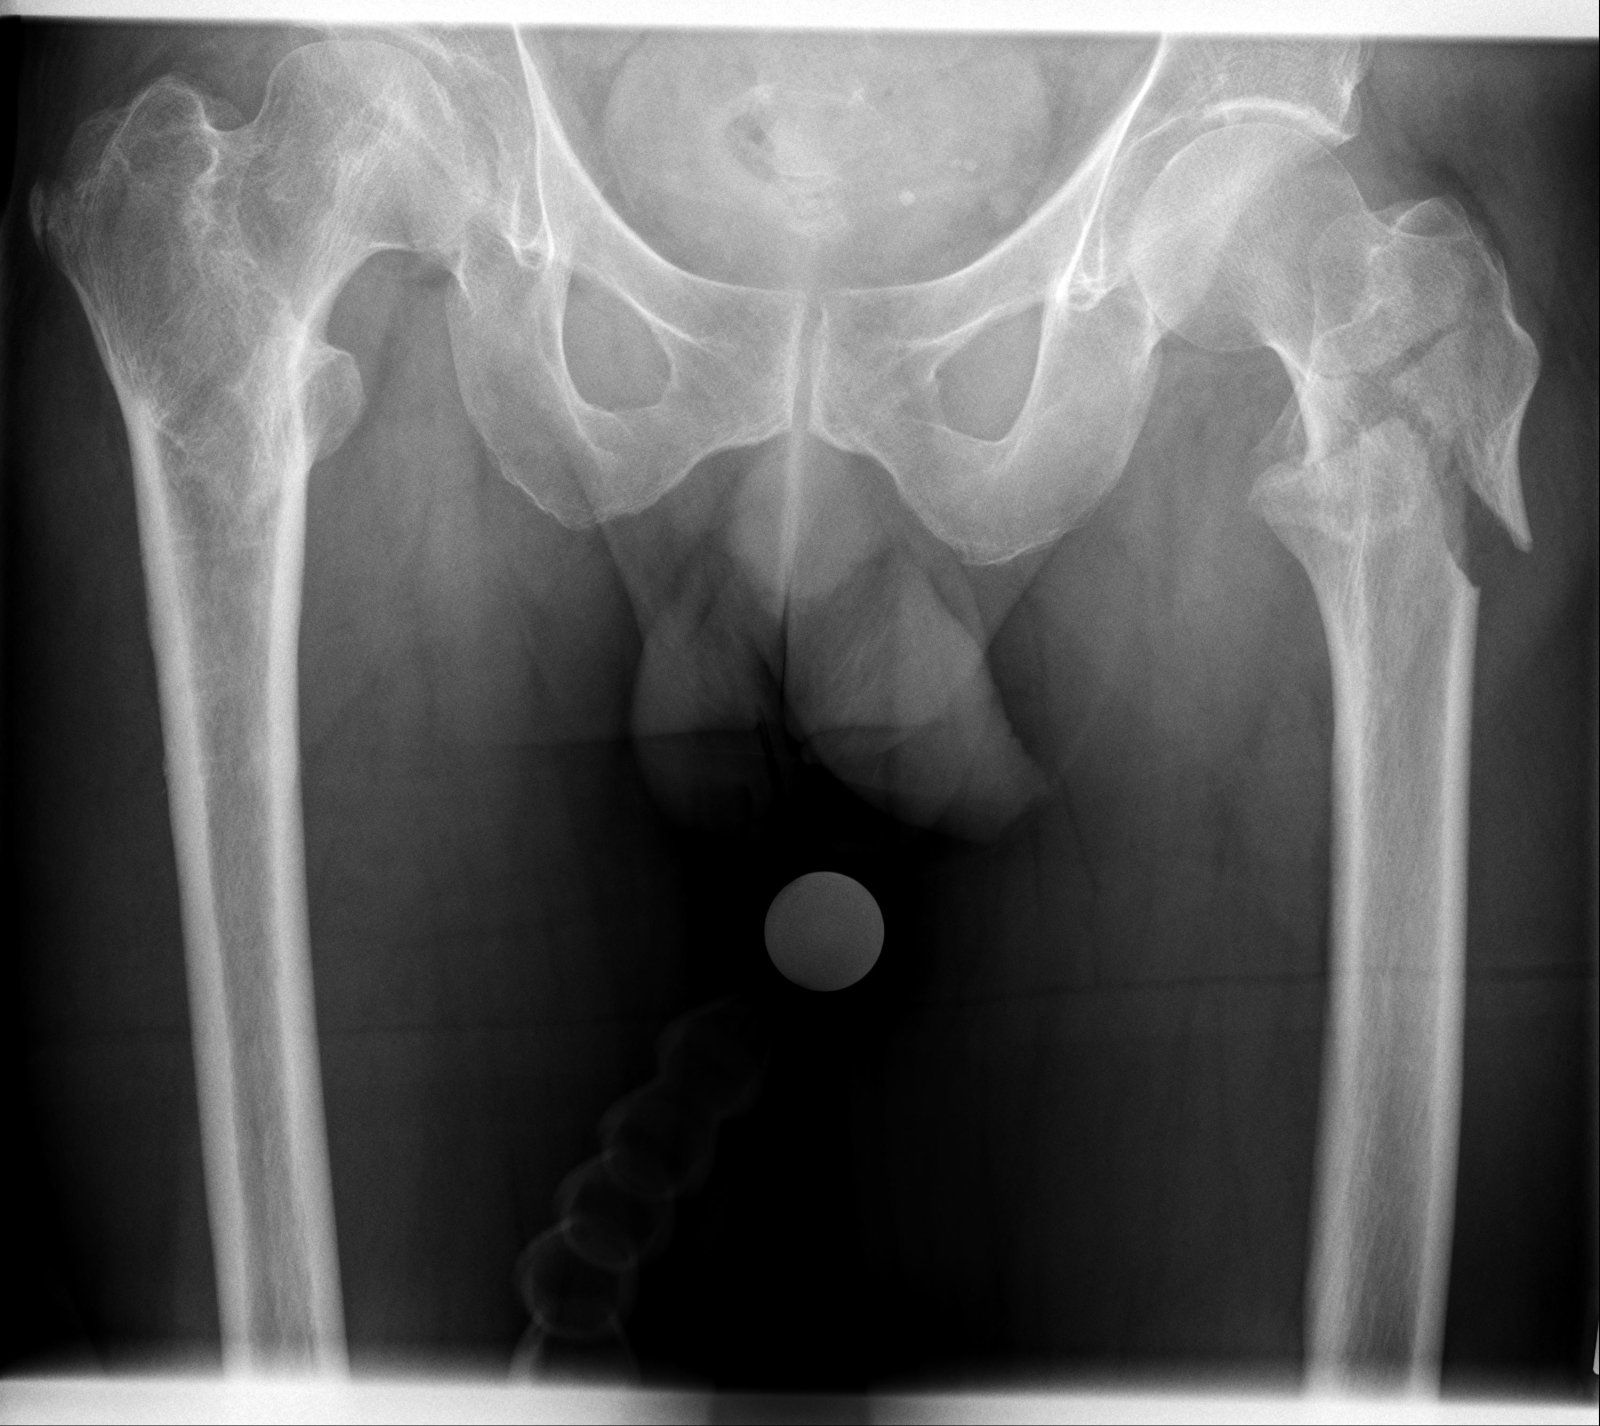

Habe heute mal die Röntgenbilder von der CD geholt.

Für nur über eine Kante gestolpert echt heftig. Habe gestern mit meiner Hausärztin gesprochen und direkt einen Cocktail aus Schmerzmittel, Vitamin D3 und Calcium verschrieben bekommen.